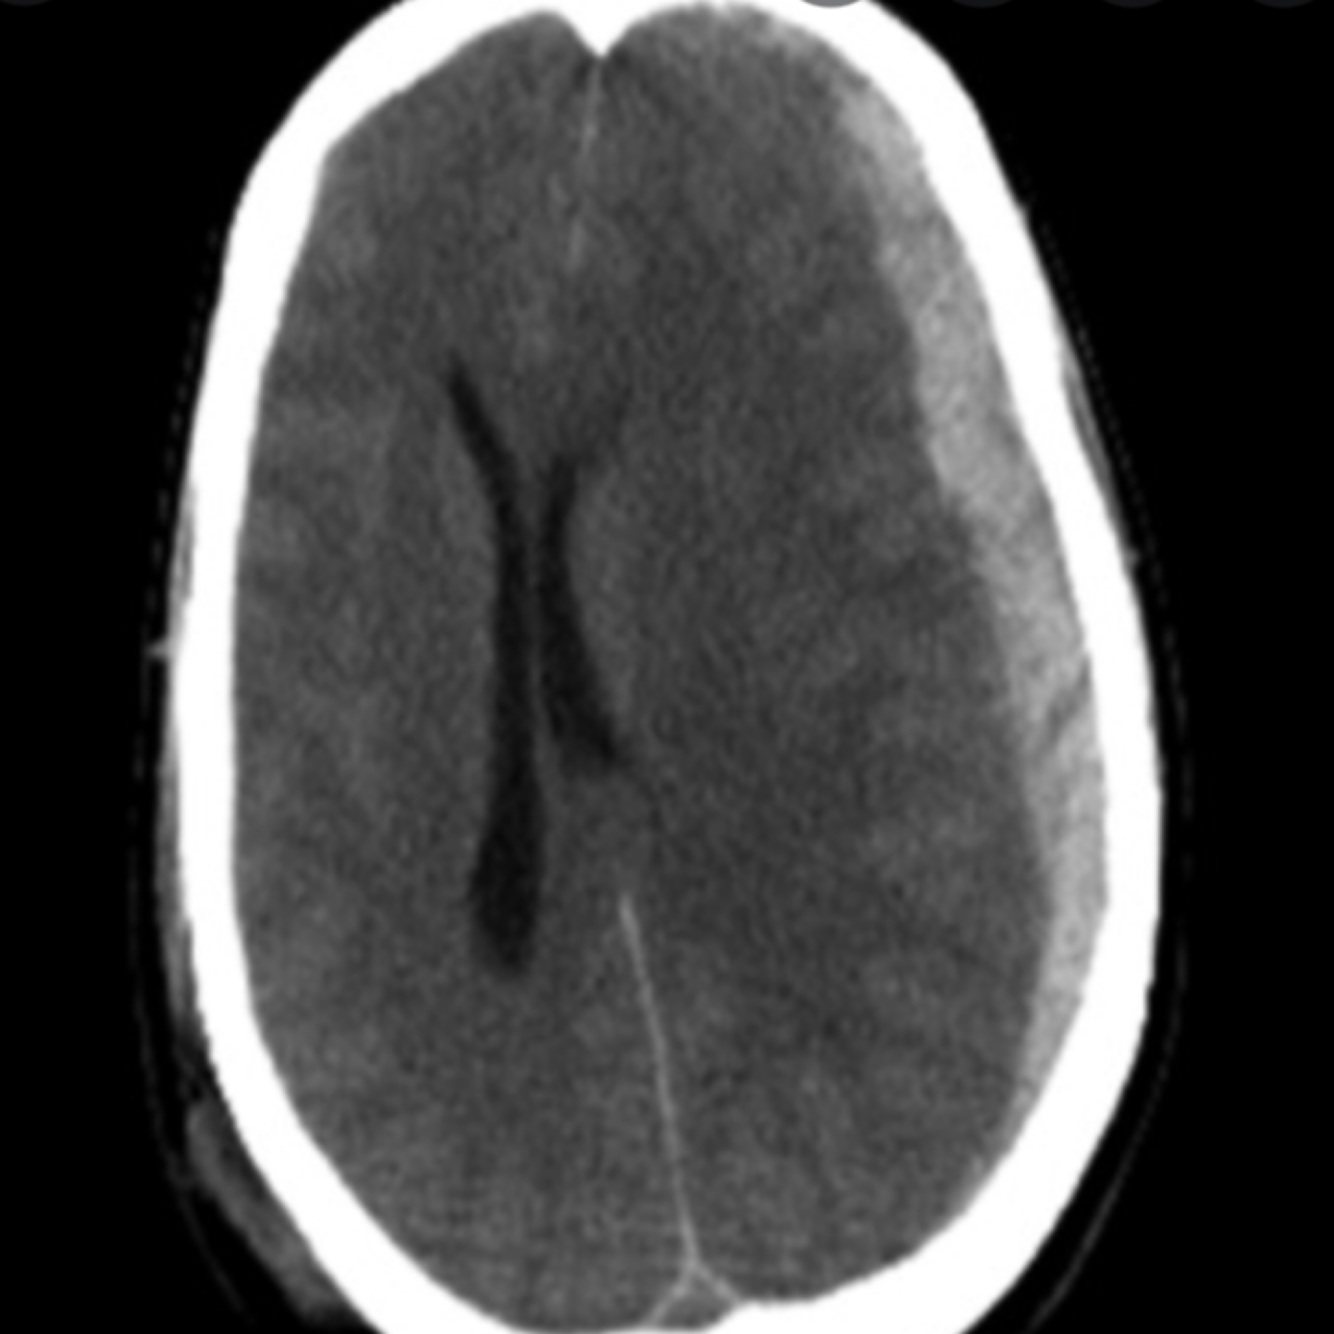

16

Q

A

Chronic subdural haemorrhage

Haemorrhage flows contour of skull as not limited by skull sutures